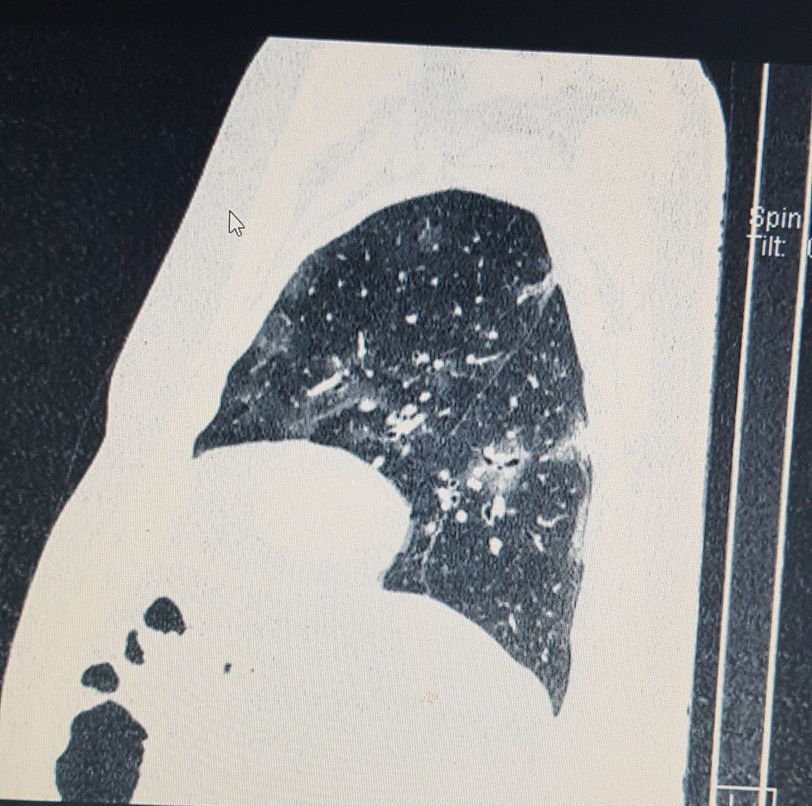

Lateral torax CT. COVID-19

Ground glass opacities.